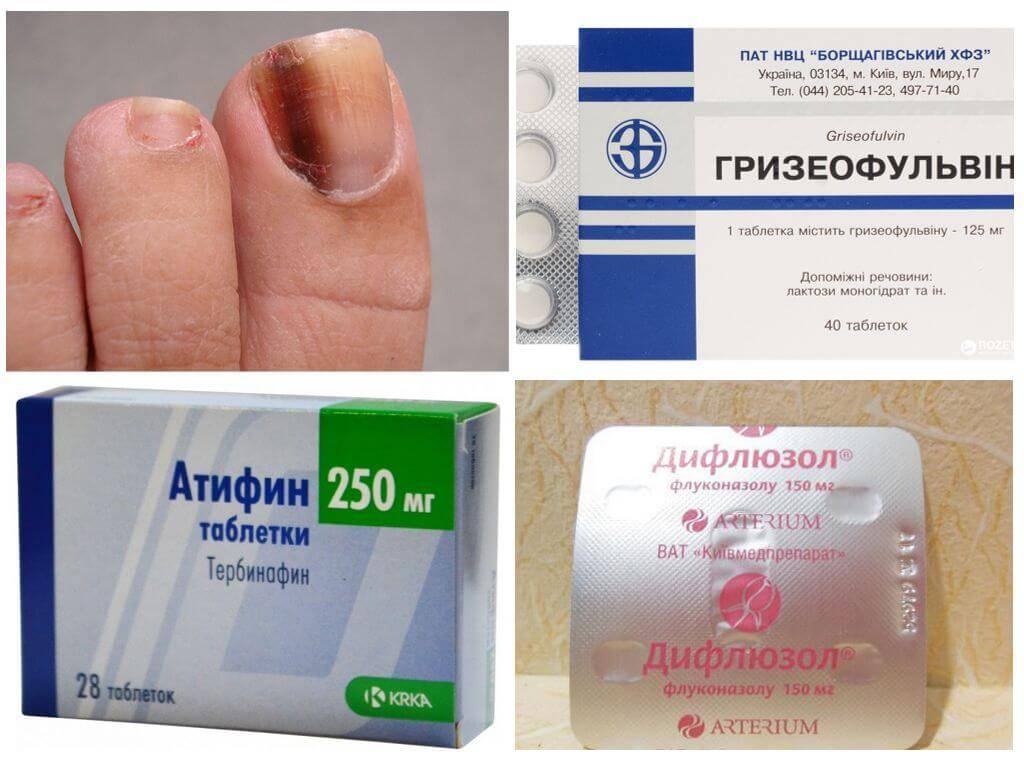

Грибковые заболевания ногтей: буклет с информацией